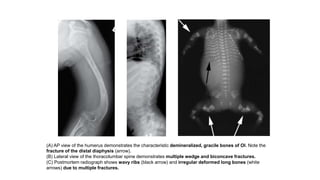

(A) AP view of the humerus demonstrates the characteristic demineralized, gracile bones of OI. Note the

fracture of the distal diaphysis (arrow).

(B) Lateral view of the thoracolumbar spine demonstrates multiple wedge and biconcave fractures.

(C) Postmortem radiograph shows wavy ribs (black arrow) and irregular deformed long bones (white

arrows) due to multiple fractures.